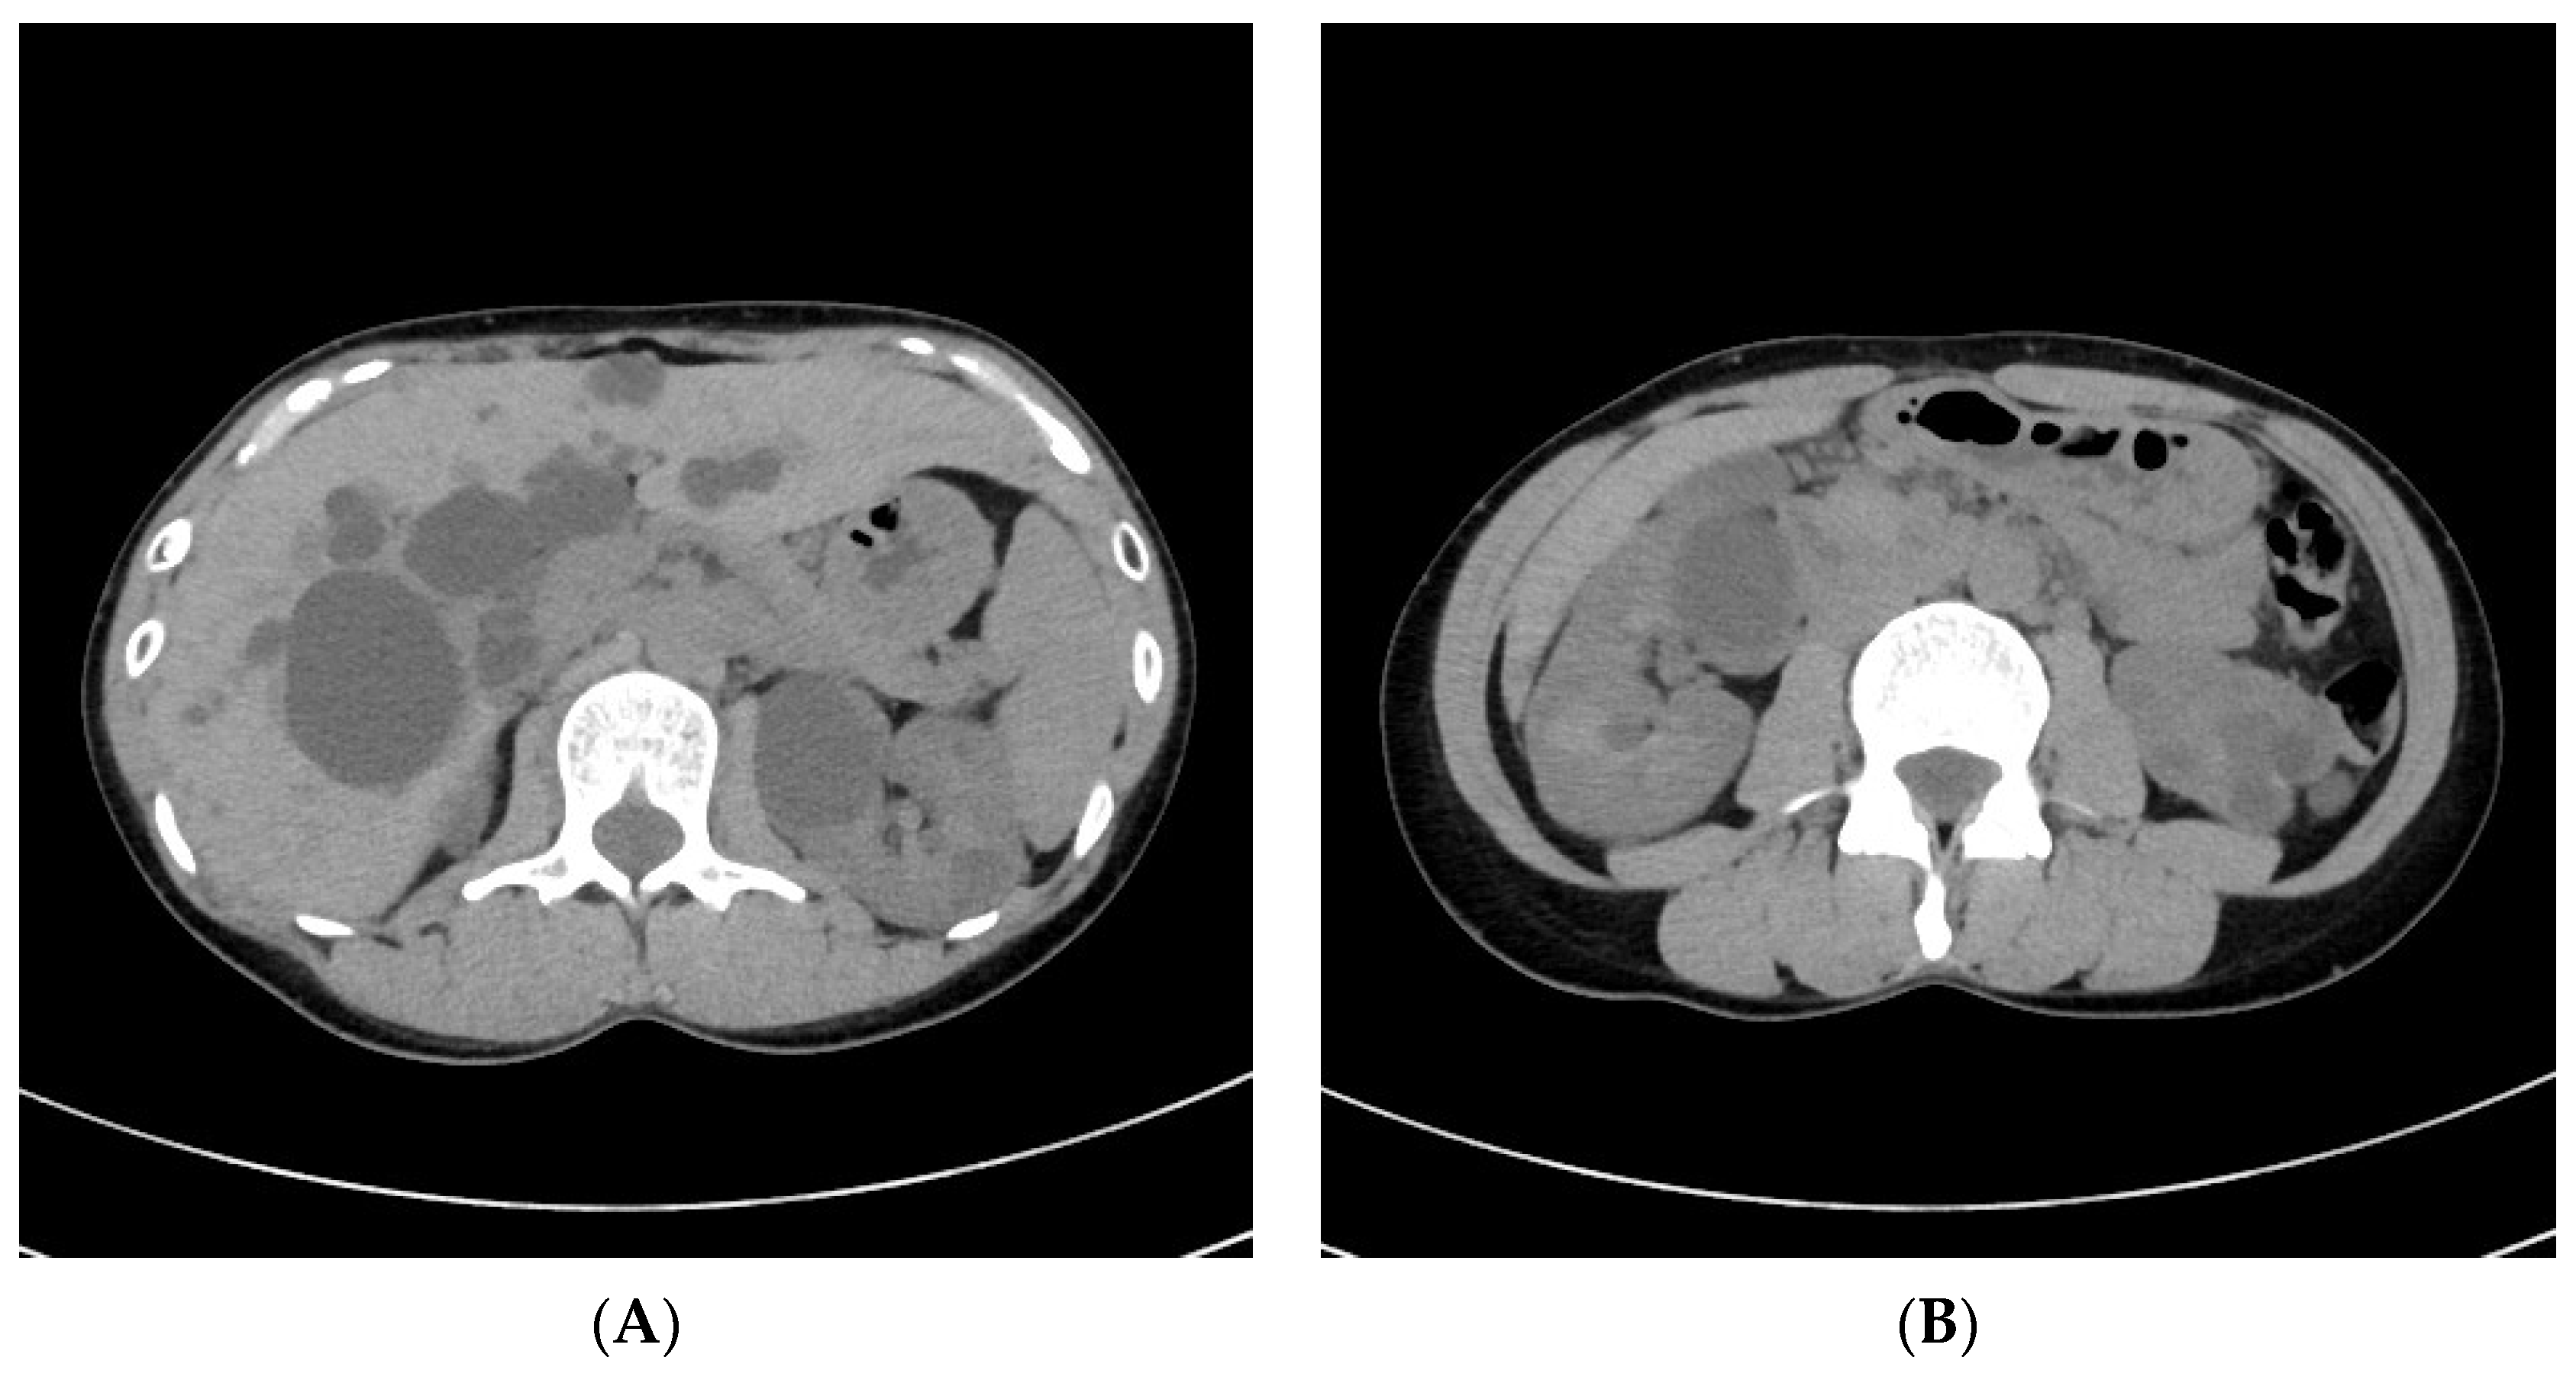

2. Illustrative Case